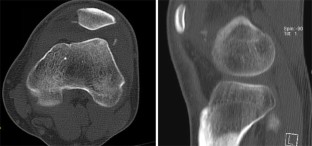

Abb. 4

Abb. 5